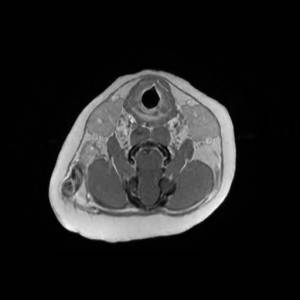

Main Gallery

Playing with a photo gallery function. It is possible to have multiple galleries, each within a namespace.